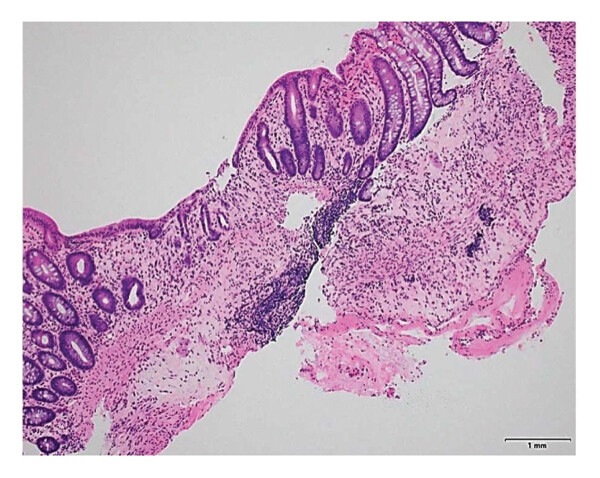

Гистологическое исследование подтвердило доброкачественный характер образования и изменениями только воспалительного характера (рис. 5 ).

Рисунок 5. Образец, полученный во время повторной биопсии, на котором заметно уменьшение признаков воспаления (выпадение и атрофия крипт, гиалинизация собственной пластинки слизистой оболочки) ГЭ;×200.